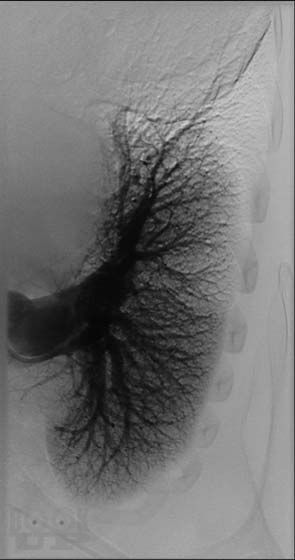

В четвертом томе четырехтомного руководства по кардиологии описываются этиология, патогенез, диагностика, клиническое течение и лечение сердечно-сосудистых заболеваний, в частности сердечной недостаточности, миокардитов, кардиомиопатий, легочной артериальной гипертензии, приобретенных пороков сердца, инфекционного эндокардита, перикардитов, опухолей и травм сердца, болезней сосудов. Приводятся также сведения об основных классах лекарственных препаратов, применяемых для лечения сердечно-сосудистых заболеваний. Руководство предназначено для кардиологов, терапевтов, врачей общей практики (семейных врачей), кардиохирургов, специалистов по рентгеноэндоваскулярной диагностике и лечению, врачей других специальностей, принимающих участие в обследовании и лечении больных с заболеваниями сердечно-сосудистой системы, и студентов высших медицинских учебных заведений.